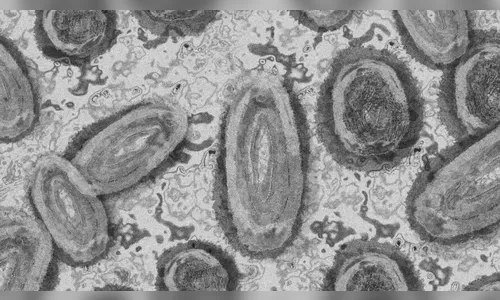

O Ministério da Saúde foi notificado sobre o oitavo caso registrado no Brasil do vírus monkeypox, conhecido como varíola dos macacos O paciente é um homem de 25 anos, morador de Maricá, no Rio de Janeiro. Ele não viajou para o exterior, mas teve contato com estrangeiros.

O caso foi confirmado pelo Laboratório de Enterovirus do Instituto Oswaldo Cruz, no Rio, que utilizou o método de Isolamento Viral para fazer o diagnóstico.

Conforme informações do Ministério da Saúde, o paciente está com quadro clínico estável, sem complicações e é monitorado pelo Instituto Nacional de Infectologia e pelas secretarias de Saúde do estado e do município.

“Todas as medidas de contenção e controle foram adotadas imediatamente após a comunicação de que se tratava de um caso suspeito de monkeypox, com o isolamento do paciente e rastreamento dos seus contatos”, informou o Ministério da Saúde, que notificou a Organização Mundial de Saúde (OMS) sobre o caso.

Dois oito casos confirmados no país até o momento, quatro foram em São Paulo, dois no Rio Grande do Sul e dois no Rio de Janeiro. Há, ainda, seis casos em investigação.

A varíola dos macacos era considerada endêmica em países da África Central e da África Ocidental, mas nos últimos meses houve relatos da doença em diversos outros países não endêmicos, especialmente na Europa, que já responde por 84% dos casos notificados, segundo a OMS.

Entre os dias 1º de janeiro e 15 de junho deste ano, a OMS foi notificada sobre 2.103 casos confirmados da varíola do macaco, em 42 países, assim como um caso provável e uma morte.